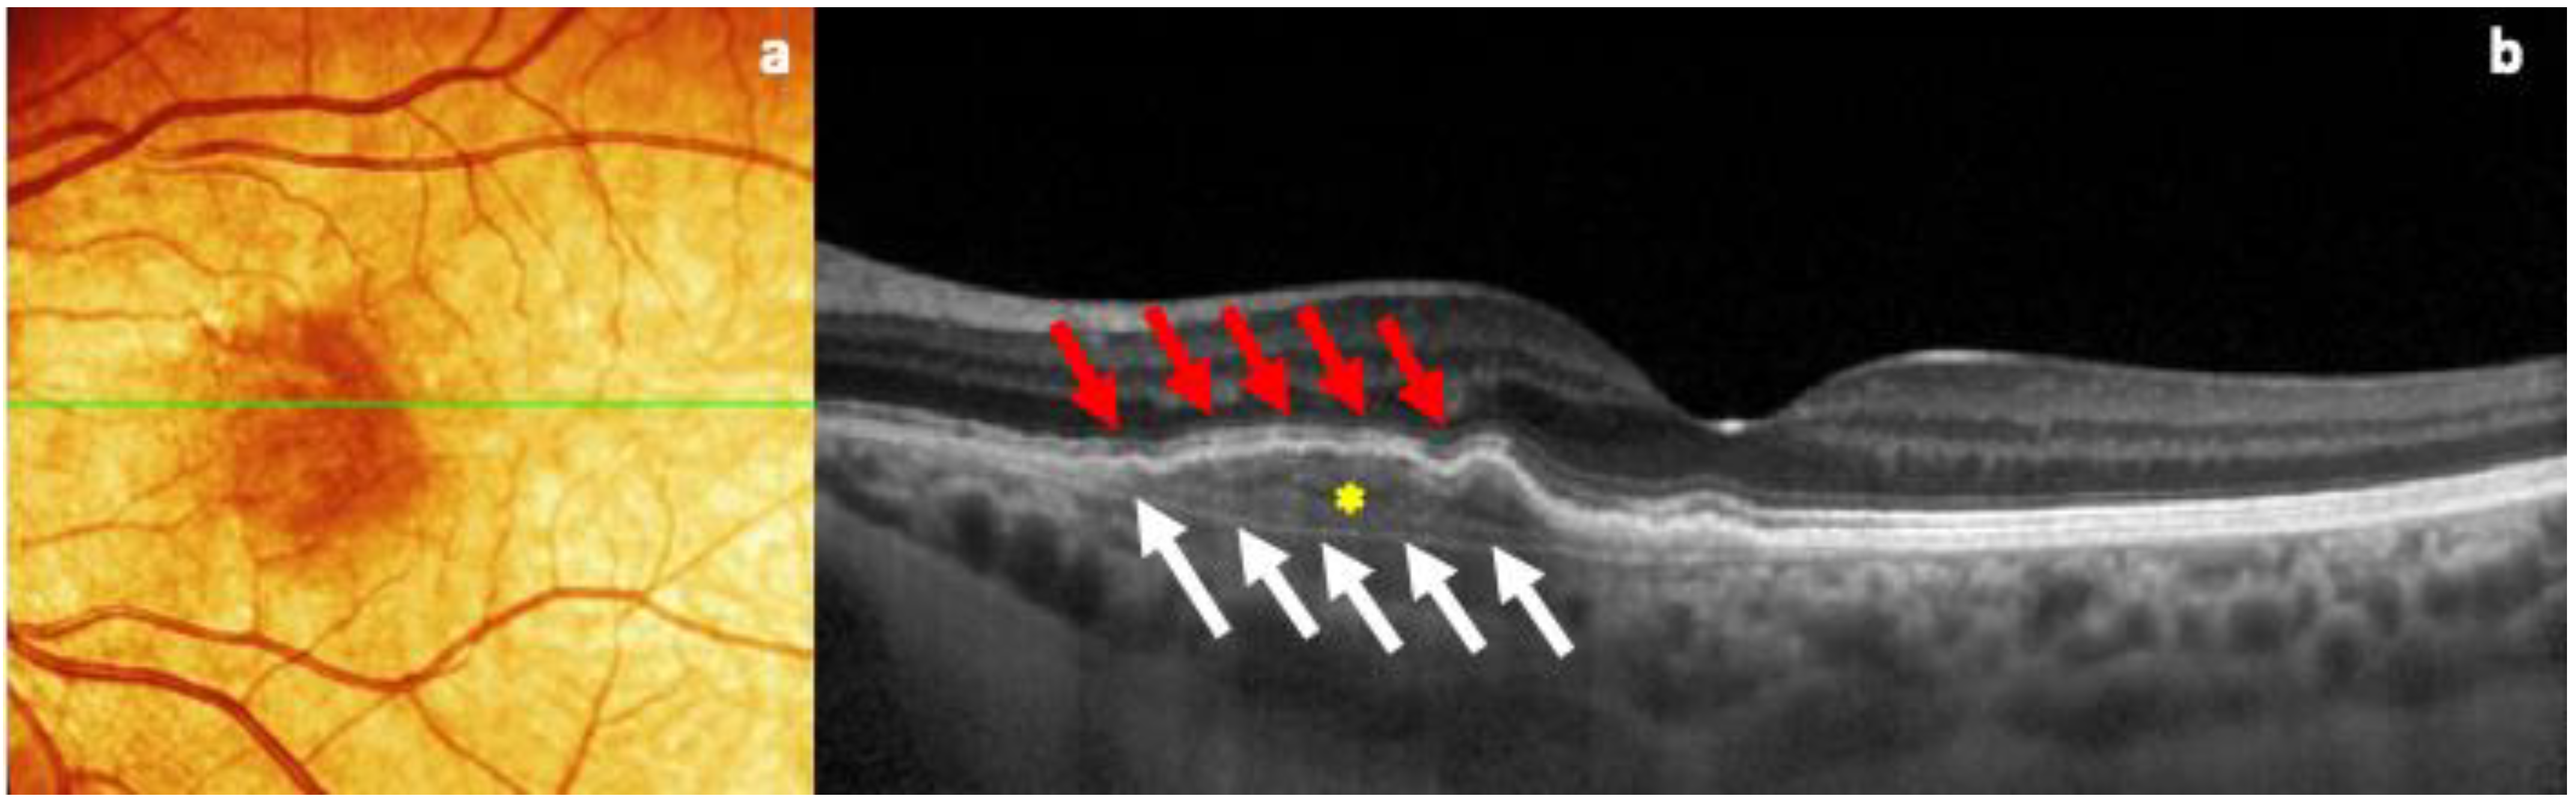

| OCT/OCTA | Presence of different signs of exudation, depending on type of MNV | Presence of two hyperreflective layers (RPE and the Bruch membrane) with a major axis on the horizontal plane, and with the presence of reflective material inside, in the absence of subretinal fluid (double-layer sign). Presence of a well-defined neovascular network, in the absence of exudation |